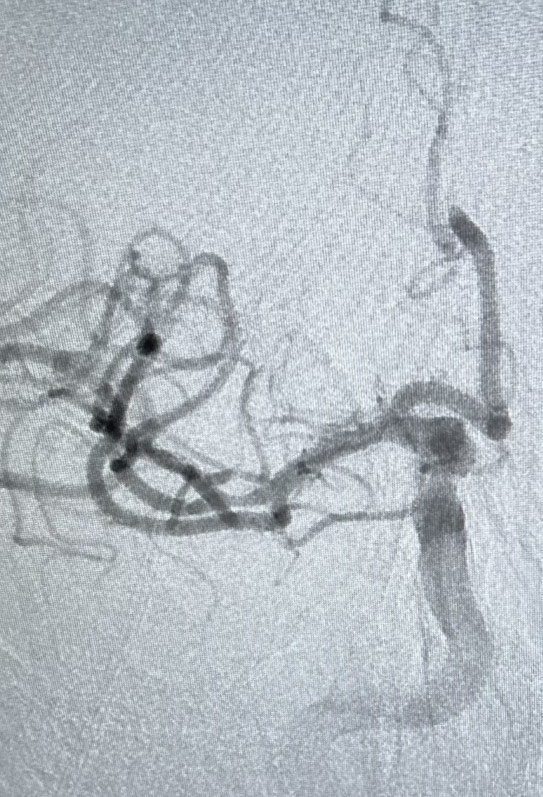

Fortunately for Ron, Banner Wyoming Medical Center’s multidisciplinary team is experienced in springing into action for severe strokes such as the one he suffered. Inside the interventional radiology suite, Dr. Bonifield accessed the common femoral artery near Ron’s groin and inserted a small guide wire covered with a vascular sheath. Guided by real-time X-ray imaging, Dr. Bonifield snaked the guide wire through Ron’s arteries and around a complex path to the artery in his neck. He then passed smaller tubes into the blocked artery in Ron’s brain and released a special device to grab the clot and remove it. After three passes, he retrieved the clot and restored blood flow to Ron’s brain.